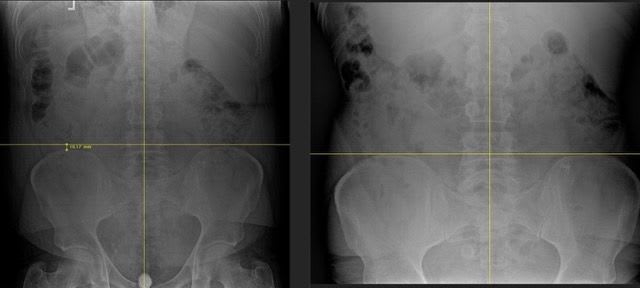

From stiffness to shooting pain down your leg, lower back issues and sciatica can disrupt your daily life. What starts as mild discomfort can quickly turn into chronic pain. Discover how to fix the root cause before it gets worse.

Even minor car accidents can cause lasting damage to your spine and nervous system, often without immediate pain. Learn why early evaluation is critical and how we correct the damage at its source.

So much of our lives put us in to bad postures and positions that over time can negatively impact our health and quality of life. At 5280 Chiropractic, we use chiropractic and exercise to correct chronic posture patterns.